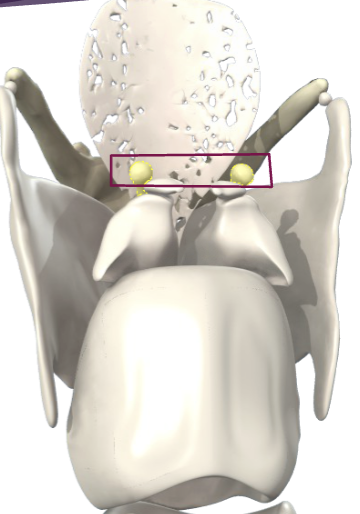

What ligament is this?

Conus elasticus

What ligament is this?

Vocal ligament

What ligament is this?

Posterior cricoarytenoid ligament